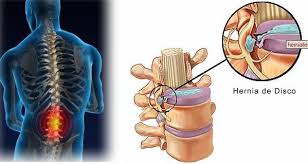

Os locais mais frequentes são a região lombar e a cervical, principalmente nas suas partes mais baixas. A hérnia de disco é muito frequente, principalmente na população adulta e idosa, embora na maior parte das vezes não cause dor ou outra queixa. Isso ocorre porque a maioria das hérnias não causa compressão das raízes nervosas.

Em algumas situações em que o disco torna-se enfraquecido ou quando ocorre uma sobrecarga da coluna (exemplo: carregar peso) há uma ruptura do anel fibroso e o núcleo pulposo ultrapassa os seus limites, sofrendo uma herniação.

Surge aí uma hérnia de disco.